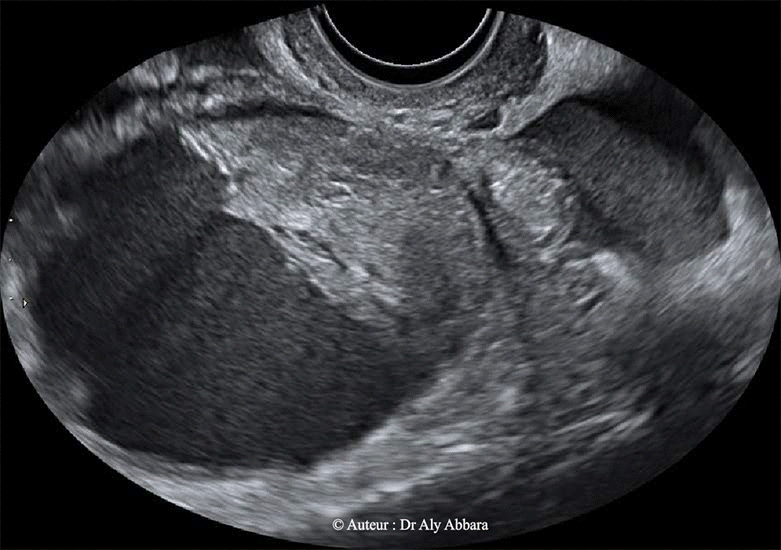

| Grossesse ectopique tubaire gauche sous forme d'amas trophoblastique au sein d'un petit épanchement péri-annexiel gauche. Évolution normale et habituelle du taux de hCG plasmatique (comme s'il s'agit d'une grossesse évolutive intra-utérine) : un dédoublement du taux de hCG plasmatique toutes les 48 heures (le taux au moment de la réalisation de cet examen échographique est 1420 UI/l) ; petit épanchement sanguin péri-tubaire gauche. Présence concomitante d'un kyste ovarien gauche d'allure fonctionnelle avec un contenu évoquant la présence d'une hémorragie intrakystique. |